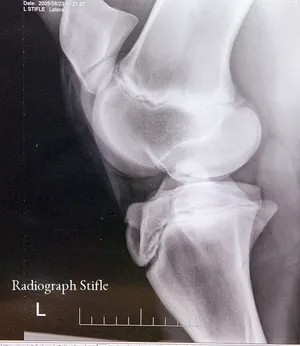

- Advanced Diagnostics & Imaging: Advanced Diagnostics, Diagnostic Imaging, Digital Radiography, Digital Radiology, Ultrasound, MRI (Magnetic Resonance Imaging), Nuclear Scintigraphy (Bone Scan), Endoscopy, and Laboratory Testing.

- Sports Medicine & Orthopedics: Lameness Evaluation, Orthopedic Procedures, and Medical Care focused on the performance horse.

- State-of-the-Art Imaging: The facility is equipped with advanced diagnostic tools, including Digital Radiography, high-field MRI, and Nuclear Scintigraphy. This allows for unparalleled detail in diagnosing subtle or complicated conditions like challenging lameness issues or internal medical problems.

- Focus on the Equine Athlete: With a significant focus on Sport Horse Medicine and Lameness Evaluation, the practice is a go-to for performance horse clients needing to maximize their horse's competitive edge and ensuring a quick, safe return to work after injury.

Choosing Equine Services, PSC is a choice for peace of mind, knowing your horse is receiving some of the best care available in Kentucky. Horse owners value the combination of world-class expertise and local convenience that this facility provides. As a full-service equine hospital, they eliminate the need for owners to seek advanced diagnostics or surgical treatment elsewhere, saving valuable time during emergencies or complex cases. The ability to perform advanced procedures, from sophisticated Lameness Evaluation using Digital Radiography and MRI to complex Orthopedic Procedures, all under one roof, is a significant advantage.